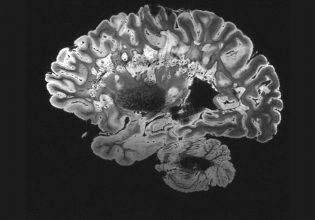

Τα αντιπηκτικά φάρμακα δεν είναι απαραίτητα μόνο στις περιπτώσεις χειρουργικών επεμβάσεων αλλά και για τη διαχείριση πολλών και διαφορετικών παθήσεων όπως οι καρδιοπάθειες, οι φλεβικές θρομβώσεις αλλά και τα εγκεφαλικά επεισόδια.

Ωστόσο οι υπάρχουσες θεραπευτικές επιλογές, όπως η ηπαρίνη και η βαρφαρίνη, συνδέονται με αρκετά σημαντικά μειονεκτήματα όπως η ανάγκη για συνεχή παρακολούθηση της πηκτικότητας του αίματος στους ασθενείς αλλά και ο κίνδυνος σοβαρής αιμορραγίας σε περίπτωση υπερδοσολογίας.

Περίπου το 15% των έκτακτων εισαγωγών στα νοσοκομεία εξαιτίας παρενεργειών φαρμάκων αφορούν επιπλοκές των αντιπηκτικών φαρμάκων. Το γεγονός αυτό υπογραμμίζει τη σημασία ανάπτυξης νέων, ασφαλέστερων και αποτελεσματικότερων θεραπειών.